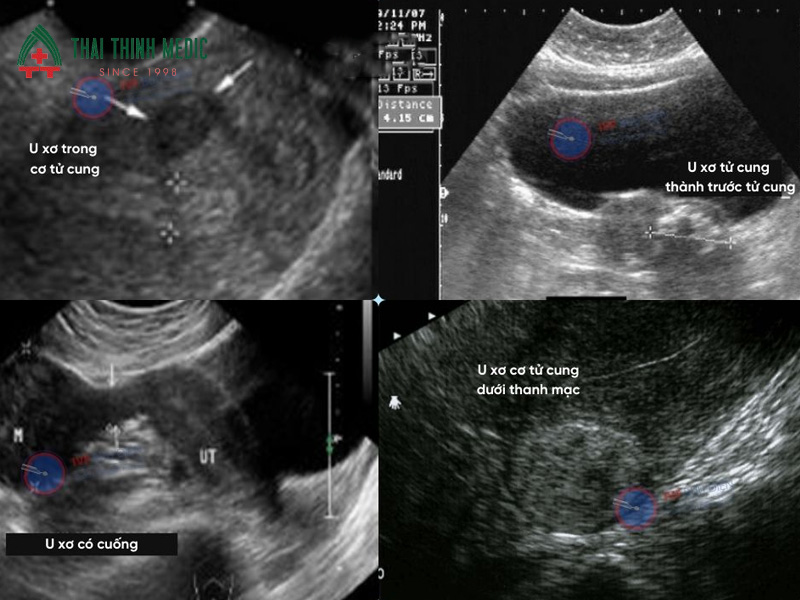

Phát hiện u xơ tử cung

U xơ tử cung là một trong những bệnh lý phụ khoa phổ biến ở phụ nữ trong độ tuổi sinh sản. Đây là khối u lành tính phát triển từ lớp cơ của tử cung và có thể gây ra nhiều triệu chứng như đau bụng dưới, rong kinh hoặc chảy máu bất thường. Tuy nhiên, trong giai đoạn đầu, u xơ tử cung thường không có dấu hiệu rõ ràng nên rất khó phát hiện nếu không thăm khám định kỳ.

Siêu âm phụ khoa giúp bác sĩ quan sát rõ cấu trúc tử cung và phát hiện các khối u nhỏ ngay từ giai đoạn sớm. Thông qua hình ảnh siêu âm, bác sĩ có thể đánh giá kích thước, vị trí và số lượng khối u để đưa ra phương án theo dõi hoặc điều trị phù hợp. Việc phát hiện sớm u xơ tử cung giúp hạn chế nguy cơ biến chứng như thiếu máu, đau vùng chậu hoặc ảnh hưởng đến khả năng sinh sản.

Nhờ khả năng quan sát chi tiết tử cung, siêu âm phụ khoa là công cụ quan trọng giúp phát hiện sớm u xơ tử cung và kiểm soát bệnh hiệu quả. Siêu âm phụ khoa giúp phát hiện u xơ tử cung thông qua:

- Quan sát kích thước và hình dạng tử cung để phát hiện khối u bất thường

- Xác định vị trí khối u trong thành tử cung, dưới niêm mạc hoặc ngoài tử cung

- Đánh giá số lượng và kích thước u xơ

- Theo dõi sự phát triển của khối u theo thời gian

- Hỗ trợ bác sĩ đưa ra phương pháp điều trị phù hợp

U xơ tử cung